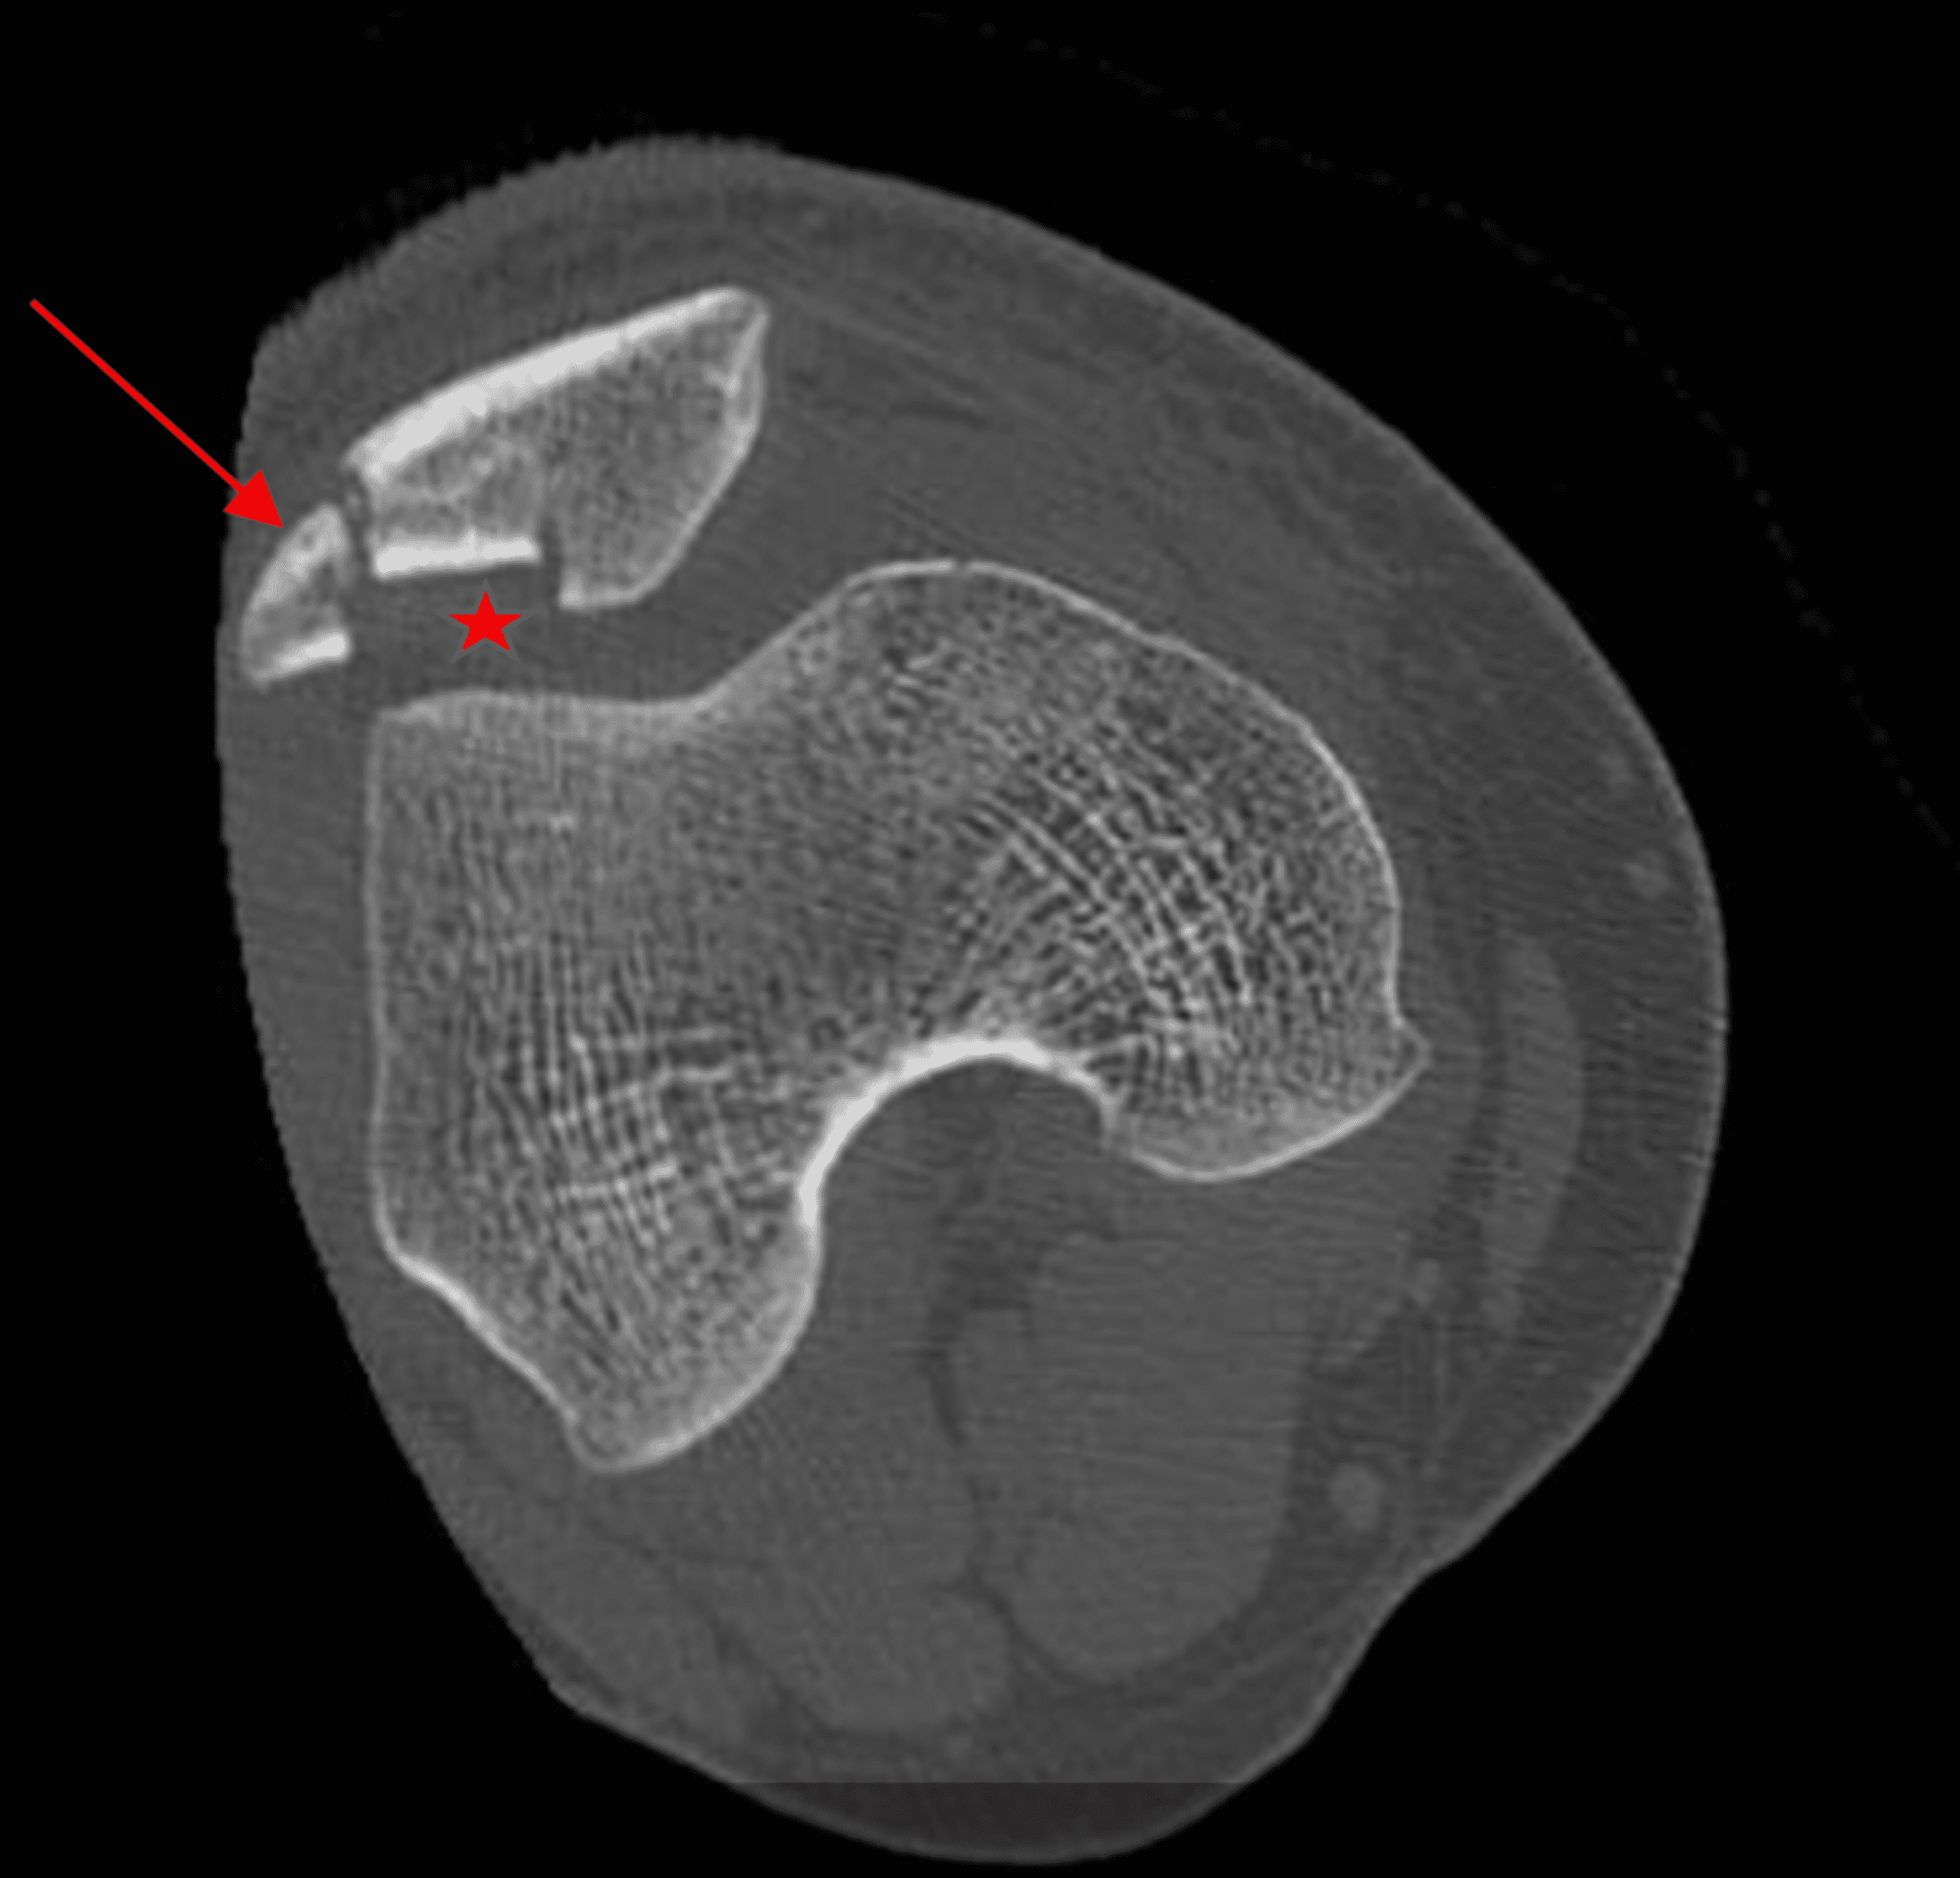

Patella fracture as a result of MPFL fixation into patella. Download Return To Sports After Patella Fracture this retrospective study presents information on functional outcome after operative treatment of patella. this recent systematic review of 27 studies found that the overall rate of return to play after mpfl reconstruction. this review focuses on return to sport after one episode of dislocation. this retrospective study presents information on functional outcome after operative treatment of. Return To Sports After Patella Fracture.

From www.researchgate.net